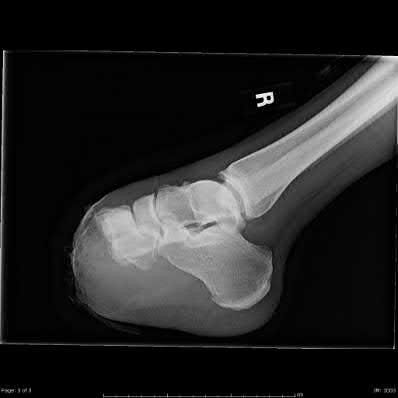

Figures 1 and 2 are the radiographs of a 68-year-old woman who comes to the emergency department after stepping into a hole and twisting her ankle. She is complaining of isolated ankle pain and is unable to bear weight.

The radiographs reveal a trimalleolar ankle fracture dislocation with an associated distal tibiofibular syndesmotic disruption. Medial and lateral malleolar stabilization are consistently agreed upon. The decision to stabilize the posterior

malleolus is more controversial. Posterior malleolar stabilization accomplishes the following:

9. Restores incisura competence thereby reducing the incidence of syndesmotic malreduction by creating containment

10. Assists in stabilizing the syndesmosis via the posterior inferior tibiofibular ligament, potentially limiting the need for additional syndesmotic stabilization

11. Maximizes the surface area for ankle joint loading

12. Enhances posterior translational stability of the talus

The traditional indication for stabilization of the posterior malleolus is based on fragment size. However, fracture orientation varies and makes evaluation of the fragment size challenging with a lateral radiograph alone. The three primary types include the posterolateral oblique, medial extension, and shell. Because of the additive syndesmotic stability which is gained through the deep deltoid ligament and medial malleolar fixation, the anterior talofibular ligament and lateral malleolar fixation, and the posterior inferior tibiofibular ligament and posterior malleolar fixation, syndesmotic stability should only be assessed after all other points of instability that are planned for fixation are fixed.

Syndesmotic instability should be assessed with direct manipulation on both the anteroposterior and lateral views with special attention to the lateral view. Syndesmotic reduction should be assessed either through open visualization or by comparing closed reduction parameters (clear space, overlap, and fibular position on the lateral view) with the patient’s contralateral side (assuming no injury). This is more effective than using population norms secondary to the two types of syndesmotic morphologies which create different absolute values for these parameters.